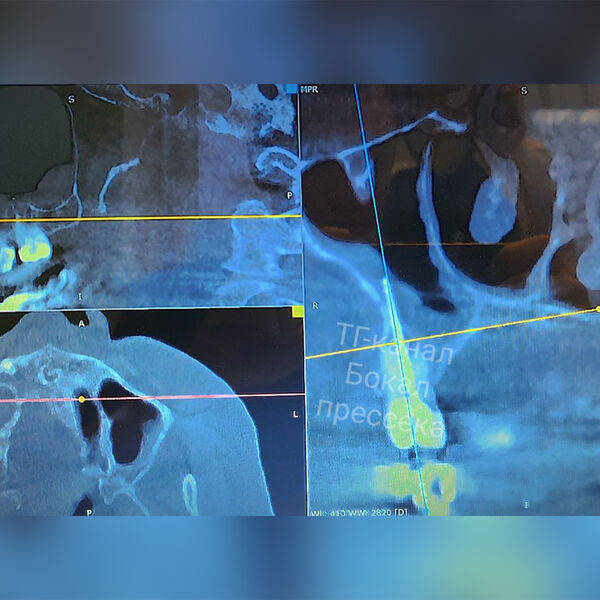

В итоге нижегородец обратился с жалобами в отделение челюстно-лицевой хирургии Нижегородской областной клинической больницы им. Н. А. Семашко. Он рассказал, что у него подозревали гайморит, но назначенная терапия облегчения не приносила. Хирурги медучреждения направили мужчину на дополнительное обследование. Во время КТ вскрылась истинная причина проблемы — боль причинял забытый отломок стоматологического инструмента. После этого часть инструмента удалили вместе с зубом, в котором он располагался.